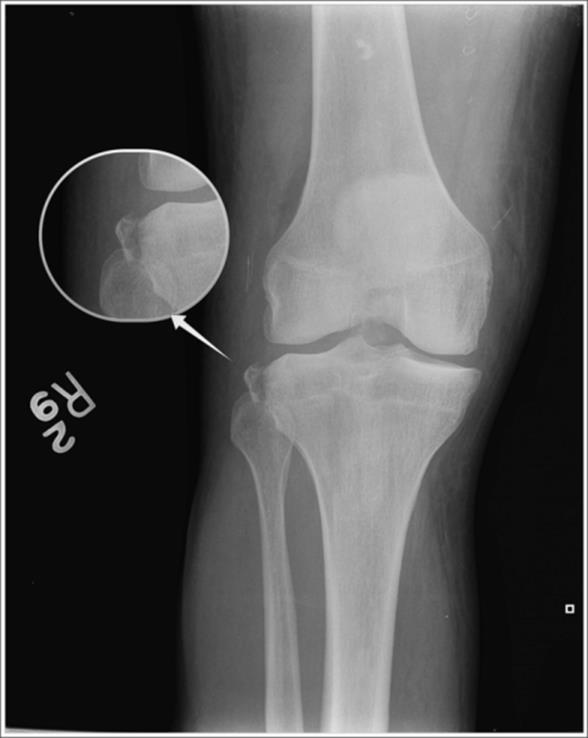

o Avulsion of the tibial spine (at the ACL insertion) (see Figure 4.7) – if seen in adults, then surgery may be indicated to anchor the avulsed fragment (this injury pattern is rarely seen in adults and more commonly seen in pediatric ACL injuries where “ligaments are stronger than bone”)

Figure 4.7 Avulsion of the tibial spine. An uncommon radiograph finding for an adult with an ACL tear. This finding is more typically seen in children who suffer ACL tears. Fracture is highlighted by the arrow. Inset shows fracture magnified. (Image courtesy of Arun Sayal, MD.)